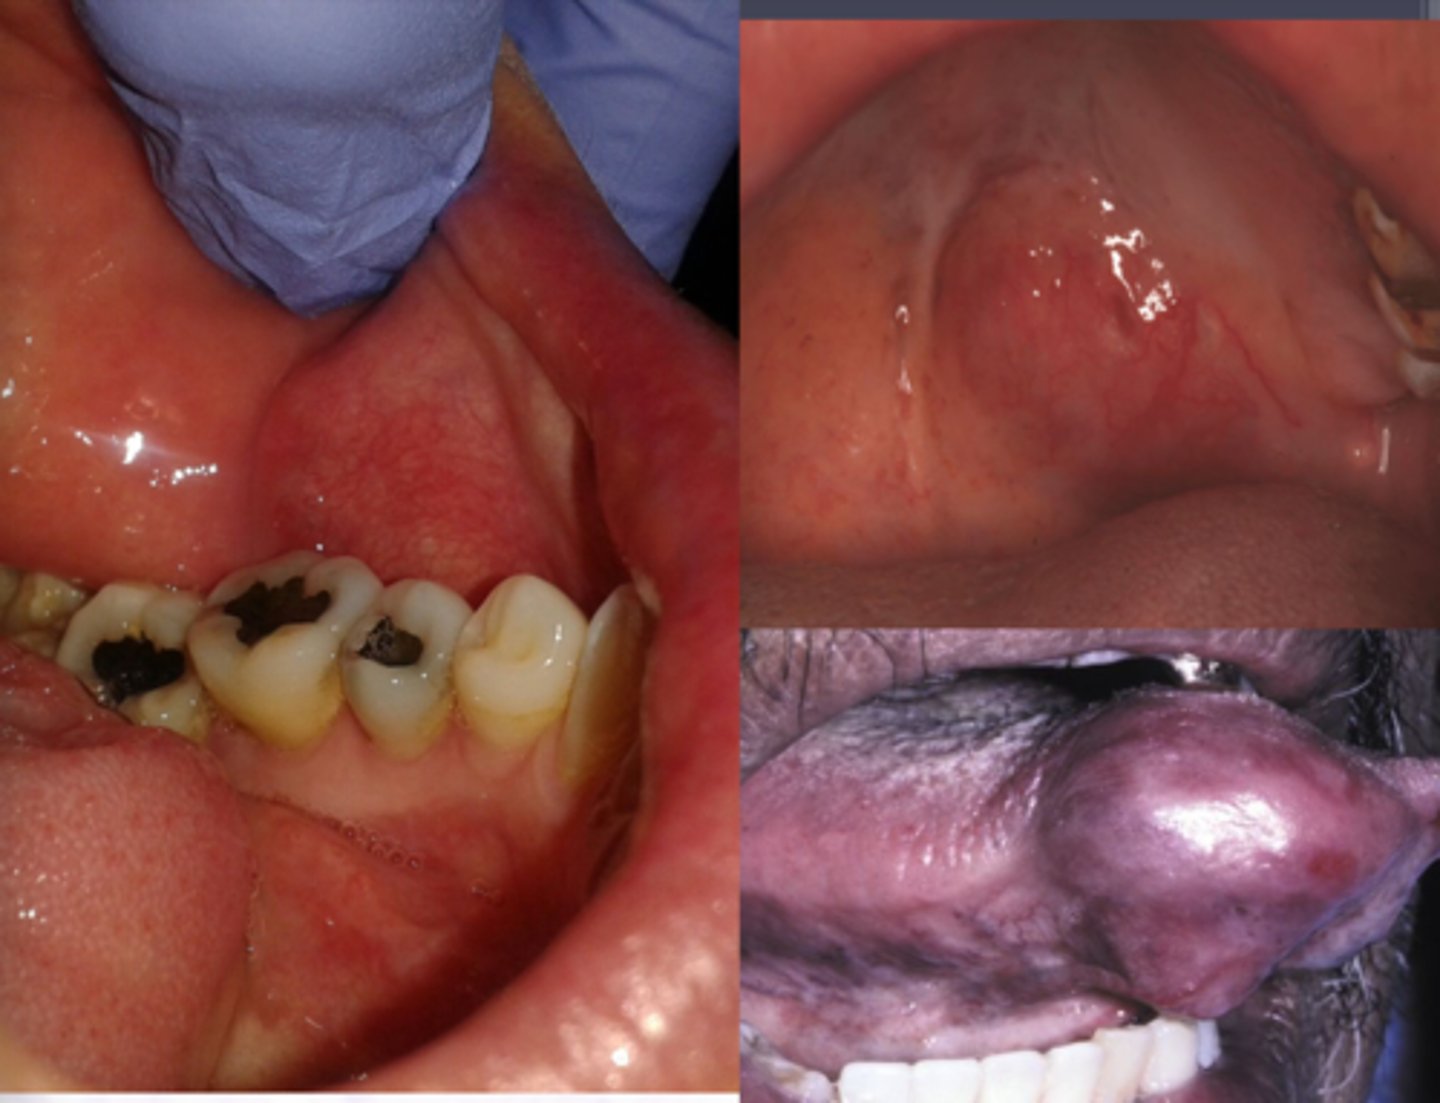

Canalicular Adenoma

Benign Salivary Gland Tumors:

Most common site is the upper lip, bluish, happens most in middle aged females >50yrs

Well encapsulated, Cell are similar in appearance, Look like canals

Basal Cell Adenoma

Uncommon, Primarily tumor of Parotid

Which condition presents a slow growing moveable tumor that is part of the superficial lobe of the parotid?

Encapsulated, Islands with

palisaded cells, Jigsaw pattern, May form ducts